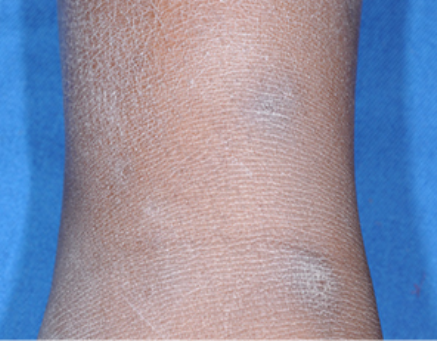

- Atopic Dermatitis